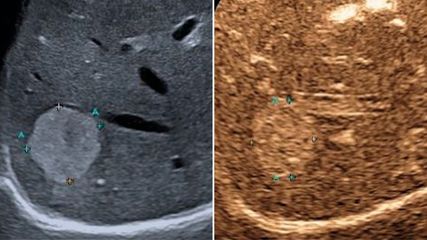

<p class="article-content"><p>Die Pankreaslipomatose wurde bereits 1926 durch Schaefer und Kollegen historisch erstbeschrieben,<sup>1</sup> blieb jedoch lange Zeit relativ unbeachtet. Mittlerweile hat sich das nahezu unaussprechliche Akronym NAFPD für den Anglizismus „non-alcoholic fatty pancreas disease“ etabliert, führt Prim. Univ.-Prof. Dr. Michael Gschwantler, Wilhelminenspital Wien, in das Thema ein. Pankreassteatose und „non-alcoholic fatty steatopancreatitis“ sind weitere in der Literatur verwendete Synonyme. Mittels bildgebender Verfahren wie Ultraschall, Computertomografie oder MRT wird eine vermehrte Fetteinlagerung im Pankreas festgestellt. Mit der zunehmenden Problematik einer weltweiten „Adipositas-Epidemie“ bekommt die Pankreaslipomatose aktuell zunehmend Beachtung. Die Häufung rezenter Publikationen dokumentiert die zunehmende Relevanz und das Interesse im Rahmen der internationalen Forschung zum metabolischen Syndrom.</p> <h2>Analogie zur nichtalkoholischen Fettlebererkrankung (NAFLD)</h2> <p>Wie bei der NAFLD ist die NAFPD eng mit der Adipositas und dem metabolischen Syndrom assoziiert und 50 % der NAFLDPatienten weisen eine Pankreaslipomatose im Ultraschall auf (Abb. 1).<sup>2</sup><br /> Sehr rezent wurden signifikante Assoziationen der NAFPD mit nahezu allen Komponenten des metabolischen Syndroms in einer Metaanalyse mit 49 329 Patienten aus 13 Studien nachgewiesen. (metabolisches Syndrom: 95 % Konfidenzintervall [KI]: 2,00–2,53; p < 0,0001; Hypertonie: 95 % KI: 1,08–1,90; p < 0,013; Diabetes mellitus: 95 % KI: 1,18–3,35; p = 0,01; „central obesity“: 95 % KI: 1,67– 2,19; p < 0,0001). Ebenso signifikant war die Assoziation von NAFPD und Fettlebererkrankung (95 % KI: 2,06–3,02; p < 0,0001). Nur ein Zusammenhang mit Hyperlipidämie wurde hier nicht direkt nachgewiesen (p = 0,249).<sup>3</sup><br /> Ebenso wie bei der NAFLD scheint ein direkter Zusammenhang mit kardiovaskulären Komplikationen zu bestehen, die morbiditäts- und mortalitätsbestimmend sind. In einer Assoziationsstudie konnte gezeigt werden, dass das Vorhandensein einer NAFPD mit vermehrten epikardialen Fetteinlagerungen und einer höheren Intima- Media-Dicke der Aorta im Vergleich zu Patienten ohne NAFPD einhergeht. Letztere ist mit subklinischer Arteriosklerose assoziiert und dient wie die Carotis-Intima- Media-Dicke als Risikomarker für kardiovaskuläre Komplikationen. In der NAFPD-Gruppe war darüber hinaus der Nüchternblutzucker signifikant höher als in der Vergleichsgruppe ohne Pankreaslipomatose.<sup>4</sup></p> <h2>Pankreasspezifische Folgen</h2> <p>Auch die exokrine Pankreasfunktion dürfte bei Patienten mit Pankreaslipomatose gestört sein. Bei 43 solcher im MRT untersuchten Patienten (ohne regelmäßigen Alkoholkonsum, Diabetes mellitus, abdominell-chirurgische Eingriffe oder chronisch-entzündliche Darmerkrankung) fand sich eine signifikant niedrigere Stuhl- Elastase-1 (319,76 vs. 549,31 μg/g; p = 0,003) und häufiger eine exokrine Pankreasinsuffizienz (Stuhl-Elastase-1 < 200 μg/g bei 11 vs. 3; p = 0,042).<sup>5</sup><br /> Länger bekannt ist bereits, dass das metabolische Syndrom und Adipositas ein erhöhtes Risiko für Pankreatitiden mit sich bringen.<sup>6</sup> Zusätzlich ist die Mortalität einer akuten Pankreatitis bei adipösen Patienten signifikant höher als bei normalgewichtigen.<sup>7</sup> Pathogenetisch könnten mit dem metabolischen Syndrom assoziierte Faktoren wie Gallensteine, Malignome, Hyperlipidämie, Medikamente<sup>8</sup> und von Adipozyten sezernierte proinflammatorische Zytokine wie Leptin, Interleukin-6, Interleukin-1β und TNFα<sup>9</sup> für die Entstehung einer akuten Pankreatitis im Rahmen der Fettleibigkeit verantwortlich sein.<br /> Auch das Risiko, ein Pankreaskarzinom als mögliche fatale Endstrecke der NAFPD zu entwickeln, könnte bei diesen Patienten erhöht sein.<sup>10</sup> Dabei ist vorerst weder ein kausaler Zusammenhang noch die Pathogenese geklärt, betont der Gastroenterologe.</p> <h2>Pathophysiologische Erklärungsansätze und offene Fragen</h2> <p>Ebenso wie bei der NAFLD führt ein Überangebot an täglich durch die Nahrung zugeführten Kalorien und westlichem Diätverhalten mit einem Übermaß an Zucker- und Fettkonsum primär zu Hyperglykämie sowie peripherer und zentraler Insulinresistenz. Dies führt analog zur NAFLD schlussendlich zu einer Lipidakkumulation in den Beta-Zellen des Pankreas. Durch das alimentäre Überangebot an freien Fettsäuren werden in der Leber vermehrt Triglyzeride synthetisiert und VLDL-Partikel gebildet, welche ebenfalls zur Lipidvermehrung in den Beta-Zellen beitragen. Dadurch kommt es in letzter Konsequenz zu vermehrtem Zelltod der Beta- Zellen und konsekutiver Abnahme der Insulinproduktion, womit sich der Circulus vitiosus schließt.<sup>11</sup> Jedoch bleibt vorerst die exakte Pathogenese weitgehend ungeklärt. Faktoren wie Insulinresistenz, oxidativer Stress, Adipokine und chronische Inflammation<sup>12</sup> werden dabei diskutiert, wie Prim. Gschwantler zusammenfasst.<br /> Offen ist auch eine klare Definition der NAFPD mit noch fehlenden und validierten Diagnosekriterien für die unterschiedlichen bildgebenden Modalitäten wie Ultraschall, Computertomografie, Magnetresonanztomografie und -spektroskopie, Ultraschall- Elastografie und Endosonografie. Derzeit stellt die MRT aufgrund ihrer hohen Spezifität und ihres Sicherheitsprofils die bevorzugte Methode dar,<sup>12</sup> bei natürlich sehr begrenzter Verfügbarkeit.</p> <h2>Natürlicher Verlauf der NAFPD analog zur NAFLD</h2> <p>Somit scheint der natürliche Verlauf der NAFPD analog dem der NAFLD zu sein. Ein Überangebot von Nahrungskalorien führt zu intrazellulärer Lipidakkumulation. Dadurch und durch das metabolische Syndrom per se (z. B. proinflammatorische Zytokine aus Adipozyten etc.) kann es zu einer chronischen Inflammation im Sinne einer nichtalkoholischen Steato-Pankreatitis (NASP) vergleichbar der nichtalkoholischen Steato-Hepatitis (NASH) kommen. Zelltod und Fibrose der Organe wären die Folgen.<br /> Die gemeinsame klinische Endstrecke beider Krankheitsentitäten stellen einerseits kardiovaskuläre Komplikationen, Organinsuffizienz bzw. Organversagen und andererseits ultimativ ein erhöhtes Karzinomrisiko dar (Abb. 1).</p> <p><img src="/custom/img/files/files_datafiles_data_Zeitungen_2019_Jatros_Infekt_1903_Weblinks_j_infekt_1903_s32_abb1_kienbacher.png" alt="" width="700" height="493" /></p> <h2>Die Zukunft der NAFPD</h2> <p>Auch bei der NAFLD war lange Zeit die Frage, ob diese Krankheitsentität überhaupt existiert, und die Diagnose wurde oftmals belächelt. Die Korrelation mit harten Outcome-Daten hinsichtlich metabolischer und onkologischer Morbidität und Mortalität ist heute jedoch bestens belegt. Interessant wird auch sein, ob aktuelle NAFLD-Therapeutika und solche, die aktuell in klinischen Studien untersucht werden, auch Vorteile für die NAFPD mit sich bringen.<br /> Sollen in Zukunft „alle“ Organe hinsichtlich Lipomatose vermessen werden? Zum Beispiel im Sinne einer „non-alcoholic fatty heart disease (NAFHD)“ oder einer „non-alcoholic fatty kidney disease (NAFKD)“? Obwohl der Gedanke zynisch anmutet, ist es doch bereits gelebte Praxis, das kardiovaskuläre Risikoprofil mittels epikardialer Fettmessung und Carotis-Intima- Media-Dicke abzuschätzen.<br /> Vorgeschlagen wird derzeit jedenfalls, das Vorliegen einer Pankreaslipomatose analog zur NAFLD als relevantes Signal für kardiovaskuläres Risiko zu betrachten, da es direkt mit dem metabolischen Syndrom und etablierten kardiovaskulären Risikomarkern wie der Intima-Media-Dicke der Aorta assoziiert ist.<sup>4</sup></p></p>